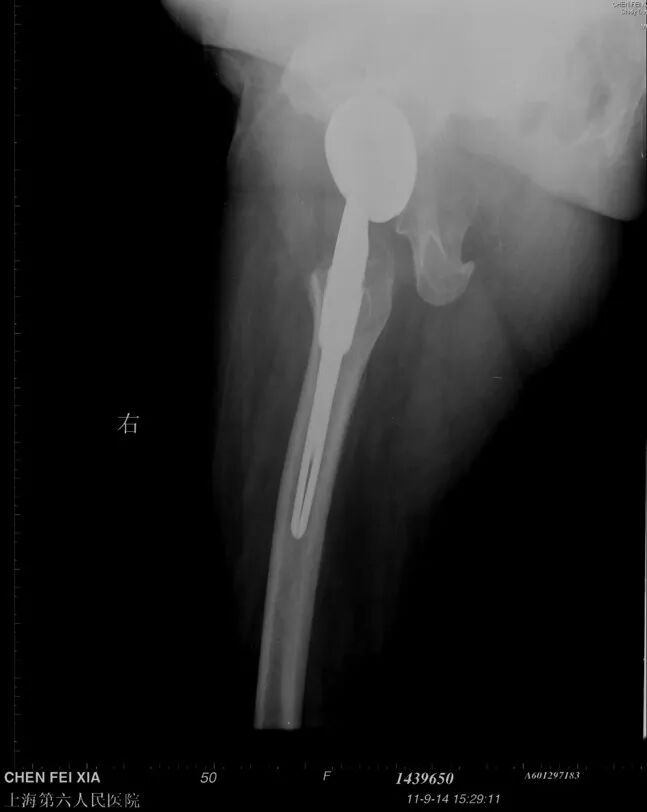

单看股骨侧,大转子顶点和股骨头旋转中心的关系恢复了

但髋臼旋转中心点上移了造成了患肢术后肢体短缩因此如果术中发现髋臼旋转中心点有上移或下移,股骨假体也应相应的吊高或下沉以获得双下肢等长

术后股骨头旋转中心点增高,导致患肢延长